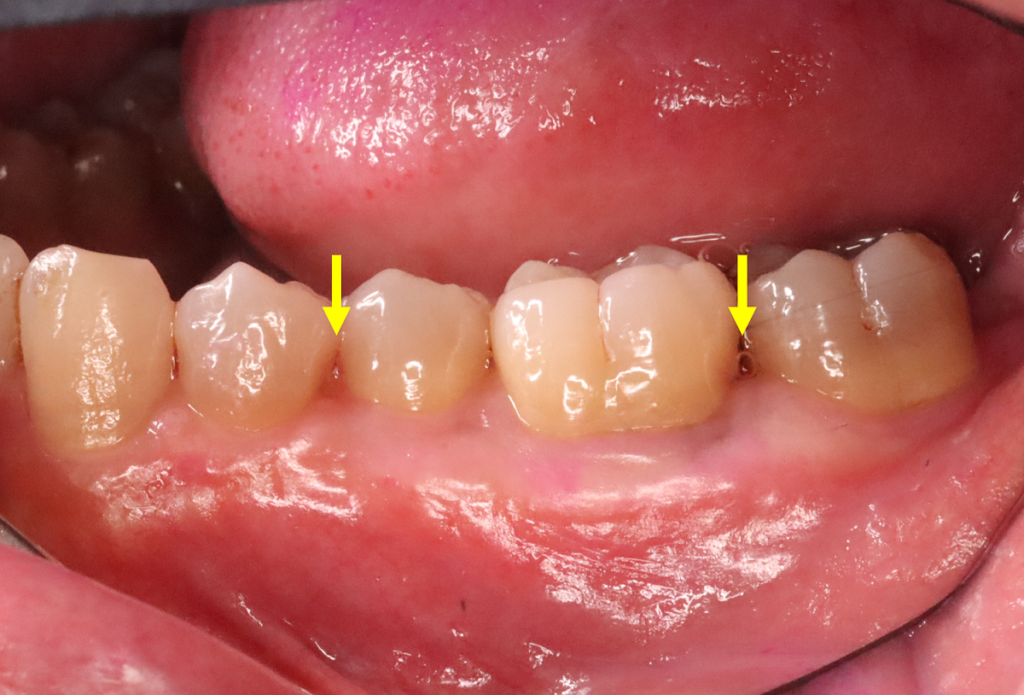

46歳男性です。

黄色い矢印のところの骨(歯槽骨)が溶けています。